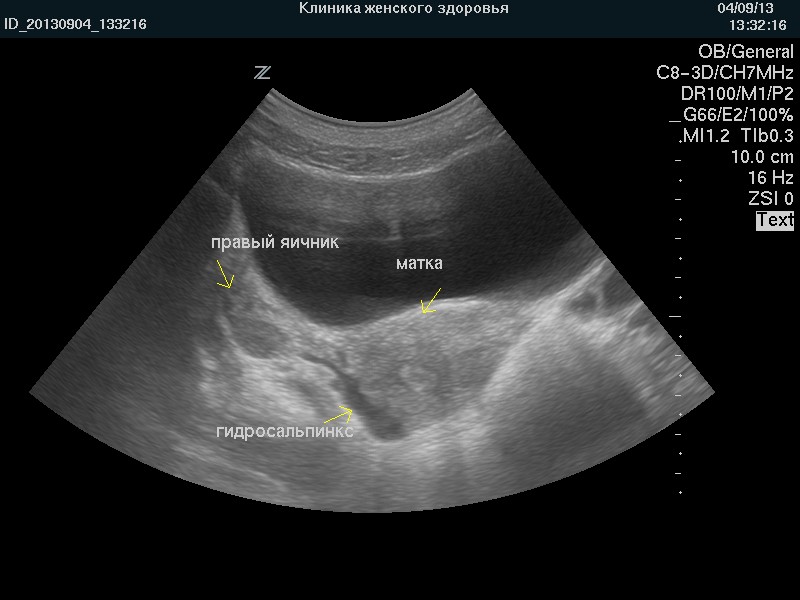

Диагностика гидросальпинкса чаще всего подтверждается с помощью ультразвукового исследования. На ультразвуковых снимках видна увеличенная фаллопиева труба с анэхогенным (не отражающим ультразвук) содержимым, то есть, заполненная жидкостью. Эта жидкость может быть однородной или содержать взвесь. В случае простого гидросальпинкса труба выглядит как мешковидное образование с тонкими стенками, при этом кровоток в них может быть нарушен, что подтверждается допплеровским ультразвуковым исследованием. При фолликулярном гидросальпинксе пораженная труба имеет вид многокамерного образования с тонкими перегородками, представляющими собой соединительнотканные тяжи. Длительность существования гидросальпинкса или агрессивность воспалительного процесса увеличивает вероятность формирования многокамерного образования.